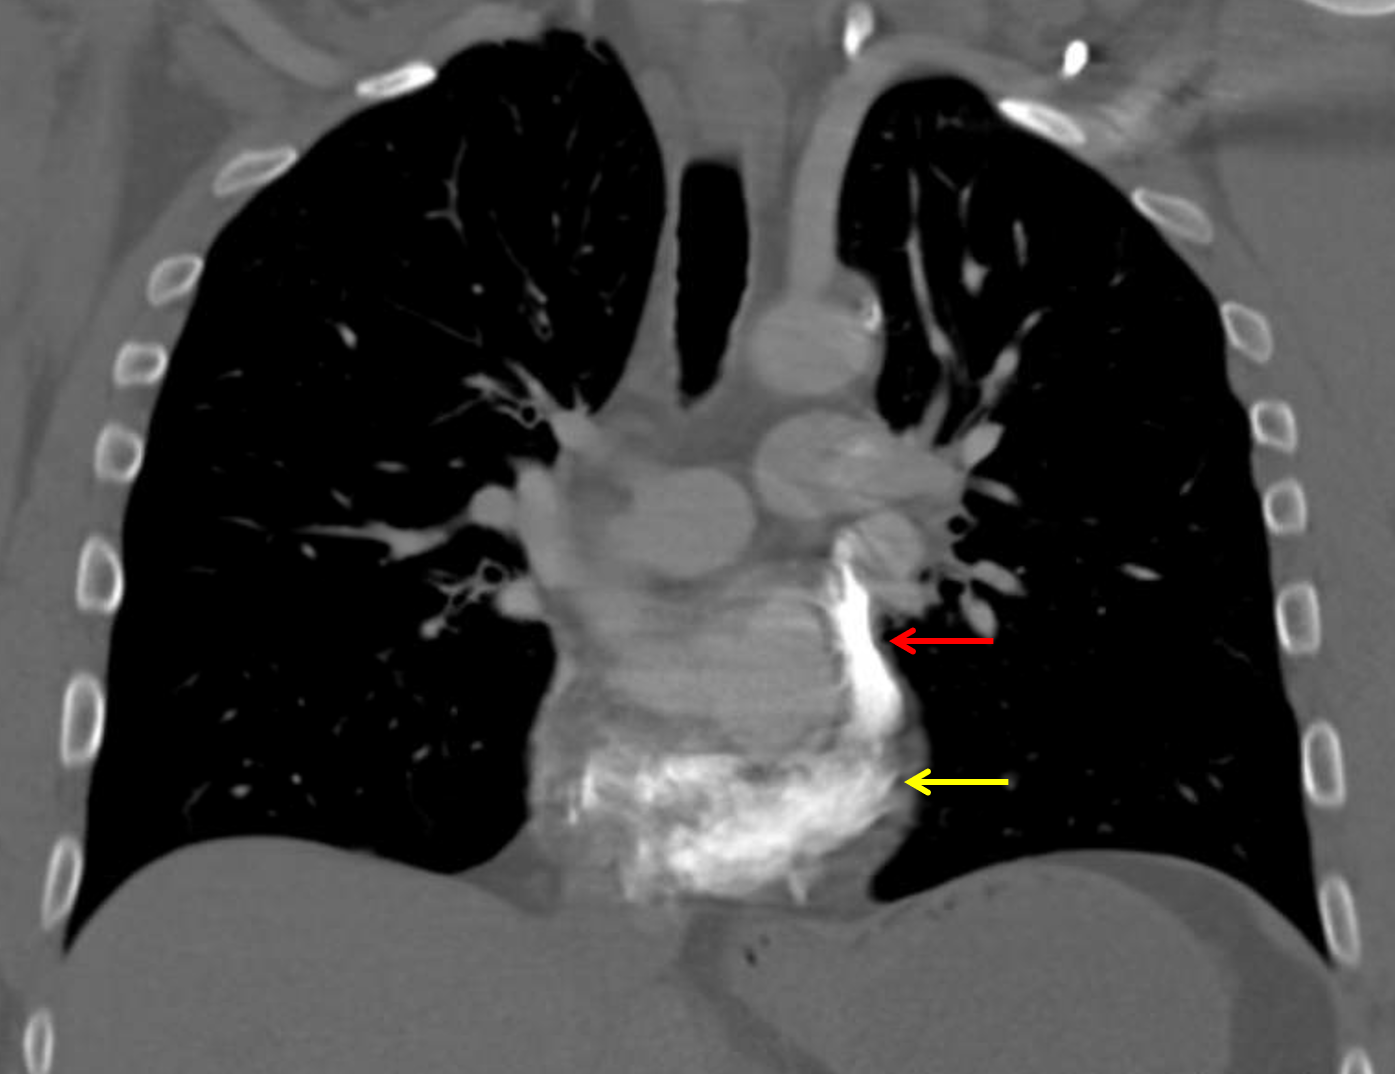

Age: 50

Sex: Male

Indication: Hemoptysis, current smoker

Sample ReportFindings suggest bronchitis and respiratory bronciolitis given the patient’s smoking history, which is the likely etiology for hemoptysis. No pulmonary mass.

Left SVC draining into the coronary sinus and absent right SVC, anatomic variant. This variant anatomy should be taken into consideration with any future central venous access.